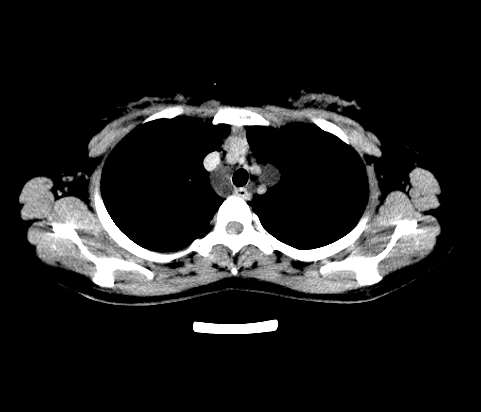

胸部